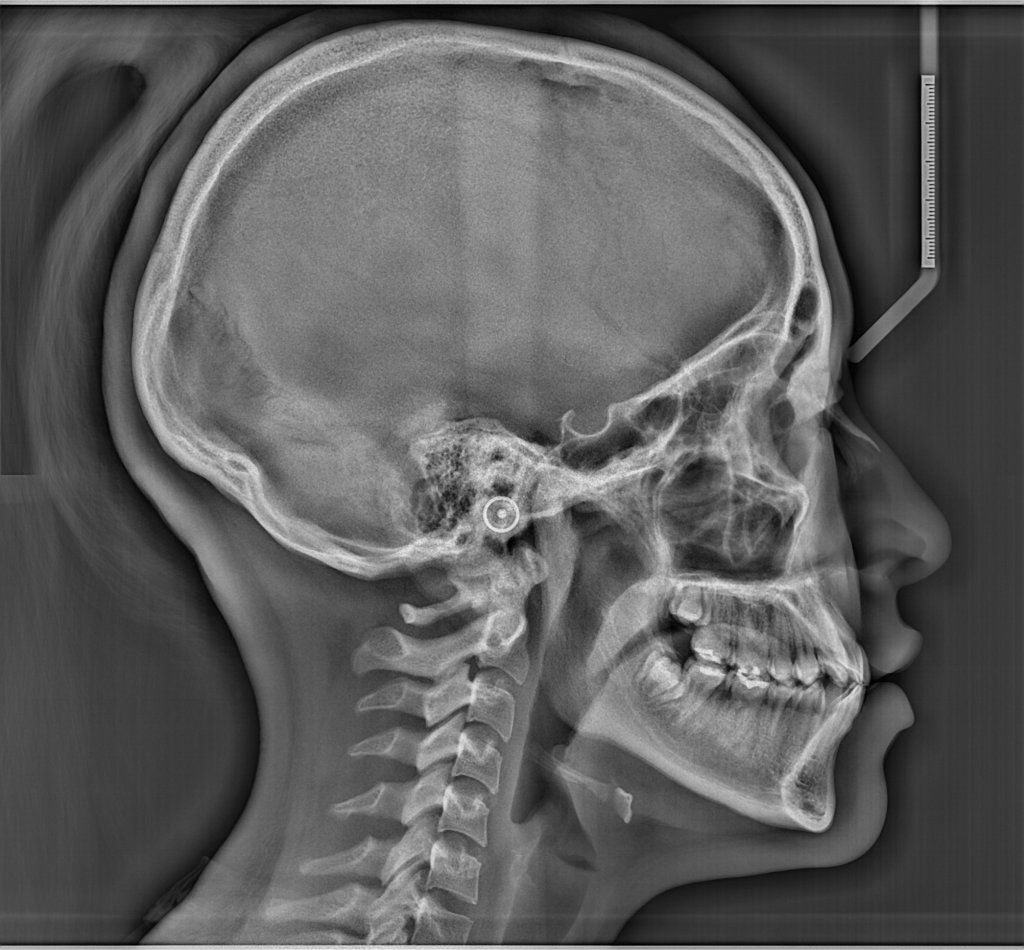

- Radiología